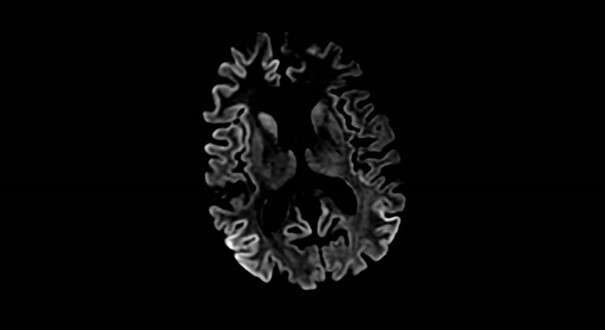

Vous réalisez une IRM cérébrale, dont voici une coupe axiale.

La clinique ainsi que le liseré cortical en hypersignal diffusion sont très évocateurs. Pour confirmer le diagnostic, mesurer le taux de protéine 14-3-3 dans le LCR (attention : prendre des précautions renforcées pour la ponction lombaire afin de ne pas contracter la pathologie). Il convient de dépister les formes génétiques. Aucun traitement n’existe à ce jour, l’évolution se fait vers l’aggravation et le décès.